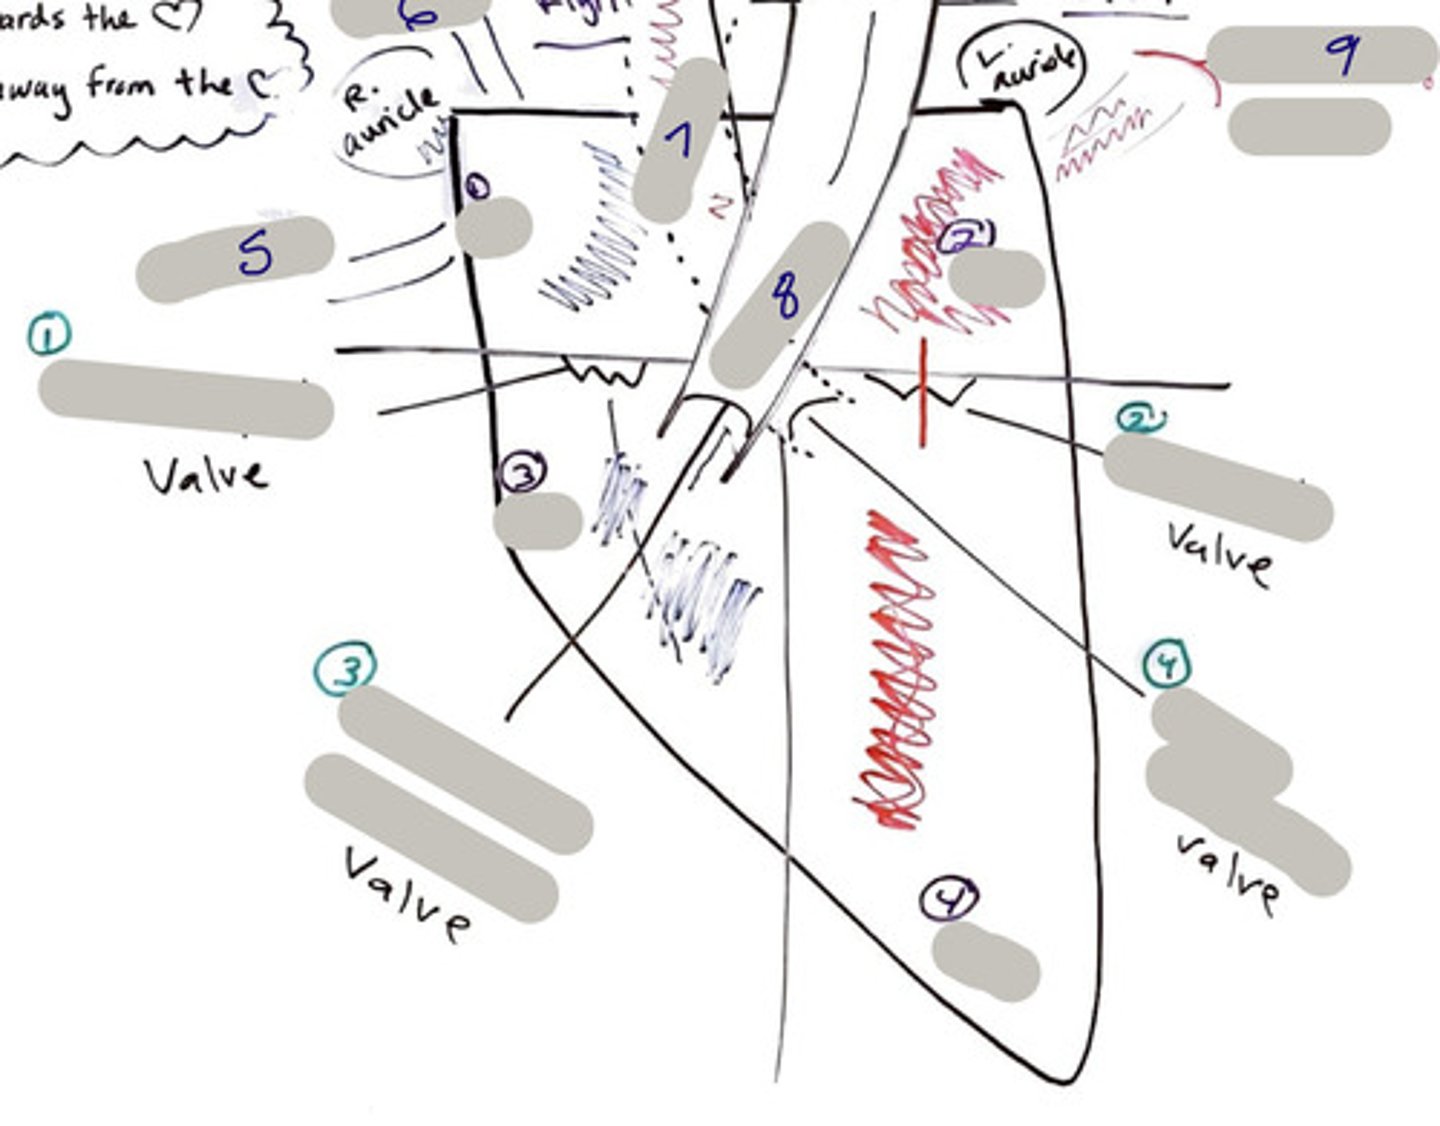

Tricuspid Valve (Right Atrioventricular Valve)

1-valve

Bicuspid valve (Left Atrioventricular Valve)

2-valve

Pulmonary Semilunar Valve

3-valve

Aortic Semilunar Valve

4-valve

Right Atrium

1-chamber

Left Atrium

2-chamber

Right Ventricle

3-chamber

Left Ventricle

4-chamber

Inferior Vena Cava

5-A vein that is the largest vein in the human body and returns blood to the right atrium of the heart from bodily parts below the diaphragm.

Superior Vena Cava

6-A vein that is the second largest vein in the human body and returns blood to the right atrium of the heart from the upper half of the body.

Aorta

7-The large arterial trunk that carries blood from the heart to be distributed by branch arteries through the body.

Pulmonary Trunk

8-carries blood from right ventricle to pulmonary arteries

Pulmonary veins

9-a vein carrying oxygenated blood from the lungs to the left atrium of the heart.